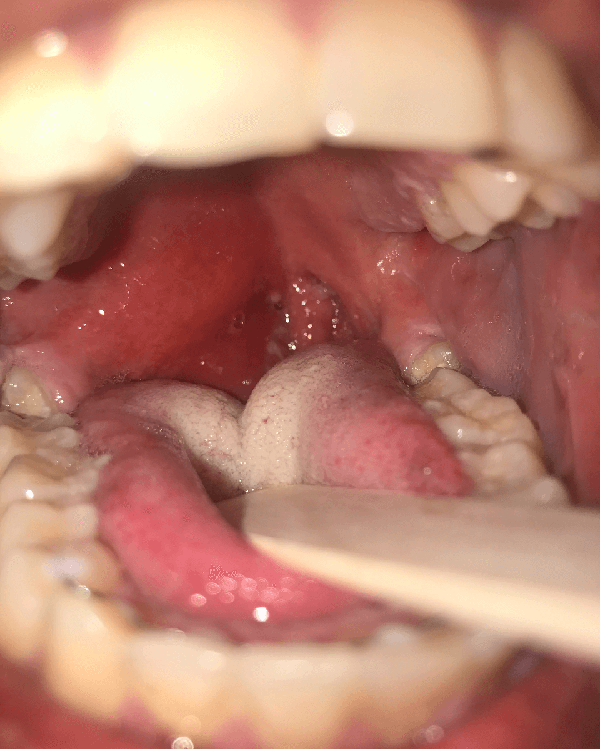

Peritonsillar Abscess